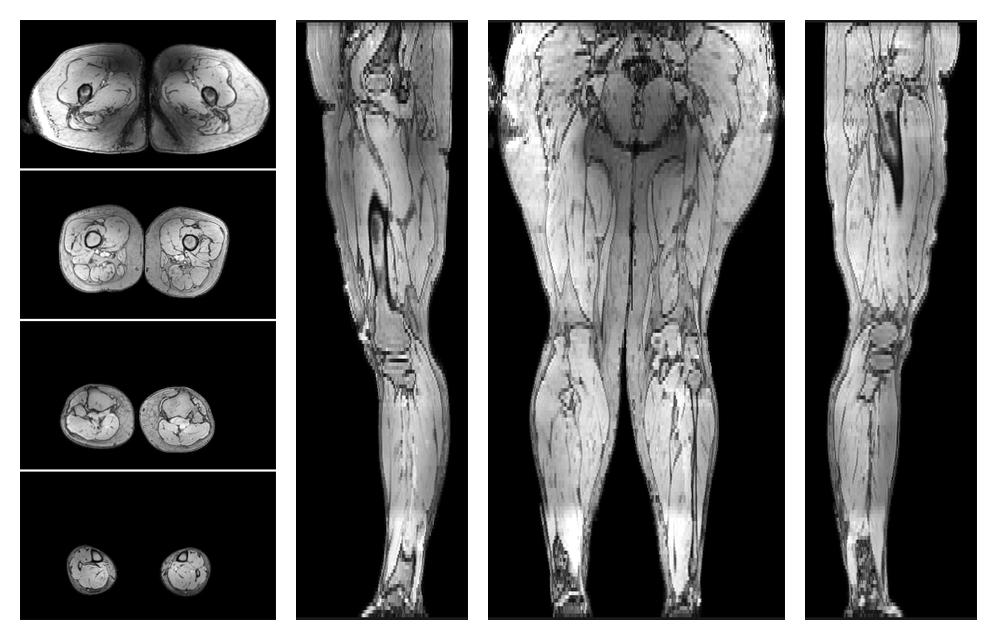

Muscle fiber tractography

Whole leg muscle fiber tractography using DTI, for information look here».

• Muscle fiber length map

Muscle fiber tract length map based on whole leg DTI based fiber tractography.

• Muscle fiber angle map

Muscle fiber tract angle map based on whole leg DTI based fiber tractography.